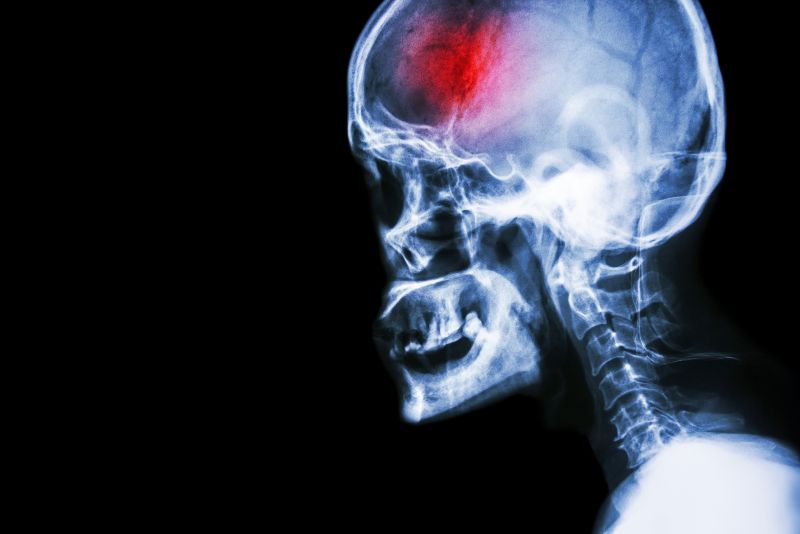

What is a stroke?

A stroke (previously known as a cerebrovascular accident) when there is a decreased flow of blood to the brain from either a blockage in the blood vessels that supply the brain (ischemic stroke), or a bleed from the blood vessels that supply the brain (hemorrhagic stroke). When the blood flow to the brain is blocked it prevents the brain from getting the needed oxygen and nutrients to function. Without oxygen the brain cells can be permanently damaged or die and the physical and mental functions related to that area of the brain will be affected. A stroke is a medical emergency and rapid treatment is crucial to decreasing the damage caused by a stroke.

Types Of Strokes

There are three types of strokes:

- Ischemic stroke: a stroke that is caused by a blockage (clot) that disturbs the blood flow to the brain.

- Hemorrhagic stroke: a stroke that is caused by a bleed that disturbs the blood flow to the brain and puts pressure on the surrounding tissue.

- Transient ischemic attack: often referred to as a “mini-stroke” or TIA, where the blood flow to the brain is temporarily disturbed and as a result causes temporary signs and symptoms of a stroke that resolve quickly .